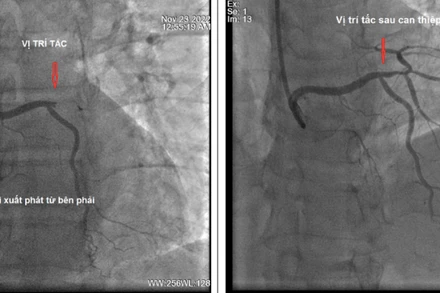

Chiều 27-11, Bệnh viện Đà Nẵng cho biết, các bác sĩ khoa Ngoại Tim mạch của bệnh viện vừa phẫu thuật thành công, cứu sống bệnh nhân T.Q.V. bị phình lóc tách thành động mạch chủ ngực cấp tính type A với nhiều biến chứng nguy kịch. Đây là một trong những phẫu thuật phức tạp, nặng nề nhất của cấp cứu ngoại khoa tim mạch.